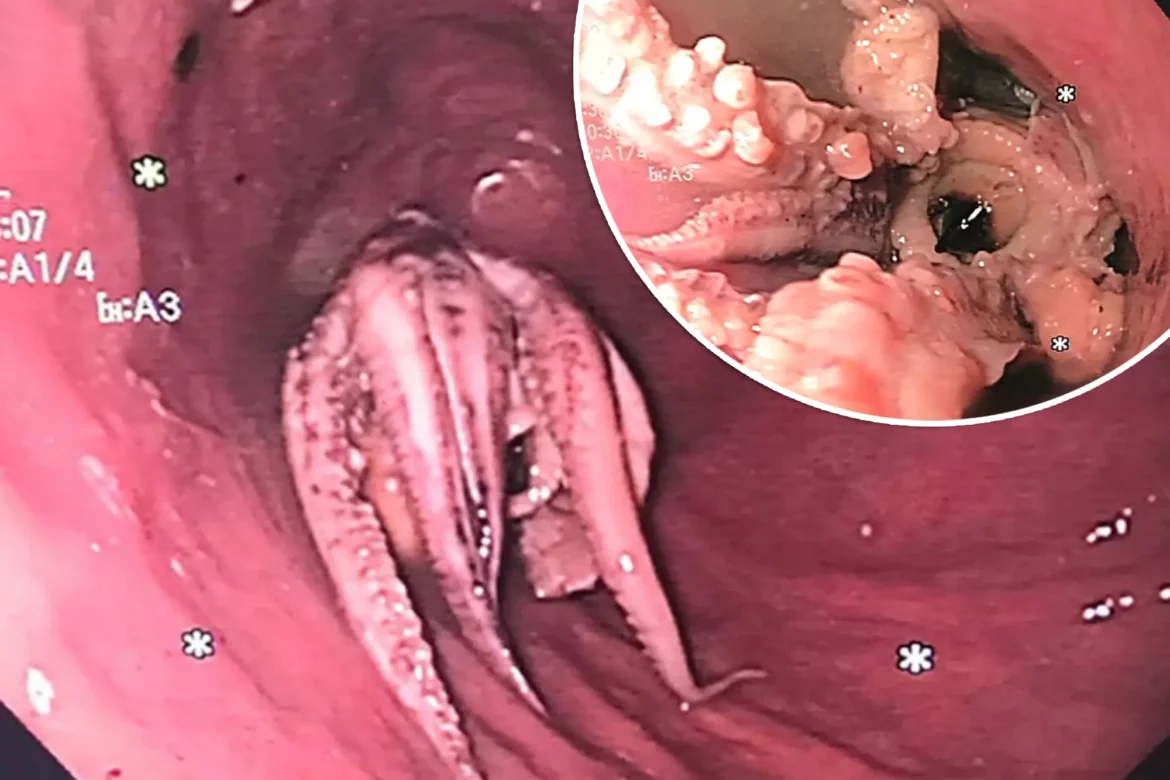

After that, the patient has an esophagogastroduodenoscopy, which is an examination of the digestive system using a small, flexible tube with a camera. This showed that the tentacled octopus was stuck 2 inches from the border between the oesophagus and the stomach.

After that, the patient has an esophagogastroduodenoscopy, which is an examination of the digestive system using a small, flexible tube with a camera. This showed that the tentacled octopus was stuck 2 inches from the border between the oesophagus and the stomach.

First efforts to push or pull out the intruder failed, so doctors used an endoscope to get around the octopus and into the stomach, where they bent it backwards. The head of the animal was then grabbed with forceps and pulled out of the person.